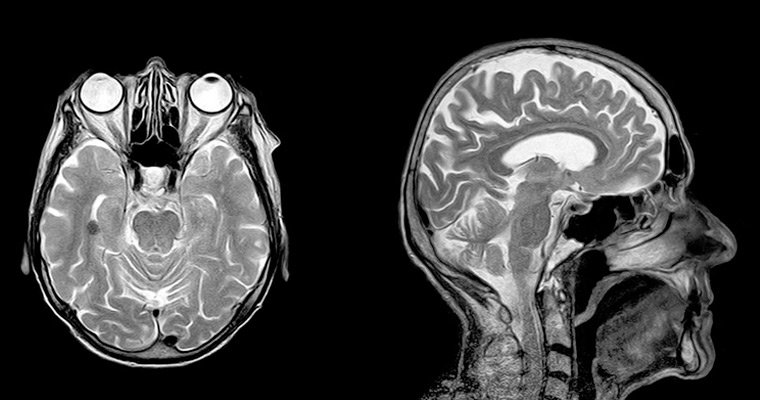

Кто назначит МРТ головного мозга

Если больного часто и сильно болит голова, то на обследование он направляется невропатологом, семейным врачом, терапевтом. При ЧМТ (черепно-мозговых травмах) направление на процедуру выдается травматологом, хирургом. Если у больного выявлены тяжелые нарушения неврологического характера, направление выписывается неврологом.

Чтобы определить работу гипофиза на МРТ направит больного эндокринолог. При необходимости документ на обследование выдается флебологом, офтальмологом, нейрохирургом и иными специалистами.

Кто расшифрует снимки, ставит диагноз

С помощью МРТ получают результаты в виде снимков с обычным и объемным изображением, которые выдаются больному. Результаты обследования записываются на USB-флеш-накопитель.

МРТ проводится рентгенологом. Врач-радиолог поможет расшифровать снимки МРТ, компьютерной томографии, рентгенографии. Специалист описывает результаты не больше 3 суток, поскольку: